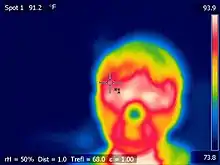

| Thermography | 1. Use the wave equation to relate the wavelengths and frequencies of the IR emitted.

2. Can you find an equation that links the temperature of the body with the frequency or wavelength of heat given off? 3. Different surfaces emit different amounts of thermal radiation. You could investigate the idea of emissivity, in the context of human tissue / skin. 4. Many thermographic cameras have an error of +/- 2%. Can you use this idea to calculate the error range in temperatures of different parts of the human body? |